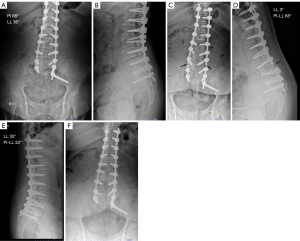

Eighty consecutive patients with mild to moderate degree of sagittal deformity, as classified by SRS classification, were retrospectively reviewed. Included patients had a mismatch between PI and LL (PI-LL mismatch) of no more than 20°, a sagittal vertical axis (SVA) of no more than 9 cm, and a pelvic tilt (PT) of no more than 30°. Each patient underwent ASD surgery with unilateral S2AI screw placement between December 2016 and June 2022, performed by a single surgeon at Thammasat University Hospital, Thailand. Inclusion criteria were ASD surgery with unilateral S2AI screw fixation, long posterior spinal fusion (≥6 levels) from the lower thoracic region to the pelvis, age ≥50 years, and a minimum 2-year follow-up. Deformity correction was planned according to the age-adjusted alignment concept (16). Deformity correction involved the interbody fusion technique and low-grade Schwab osteotomy without using the three-column osteotomy technique. In cases with coronal imbalance, the S2AI screw was inserted on the same side as the truncal shift, for the same reason as the kickstand rod technique (17). In cases without coronal imbalance, the S2AI screw side was decided by the surgeon’s preference (Figure 1). Patients with incomplete radiographic data were excluded. This retrospective cohort study was conducted in compliance of the Declaration of Helsinki and its subsequent amendments. The Human Ethics Committee of Thammasat University approved this study (approval No. MTU-EC-OT-0-296/67). The inform consent was not performed due to the nature of retrospective study.